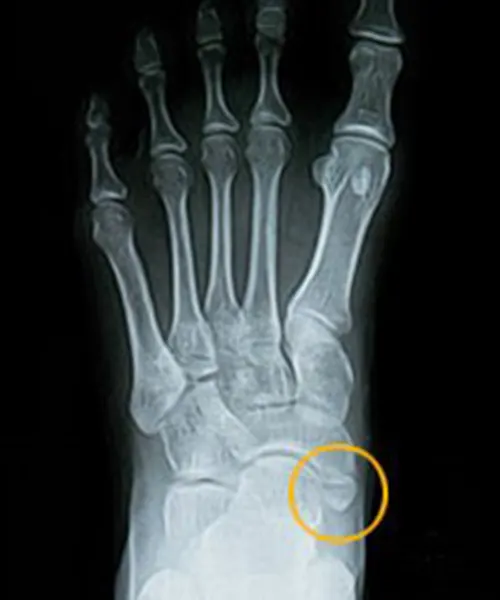

附生舟狀骨( Accessory Navicular Bone )

附生舟狀骨

也稱副舟狀骨,意思就是第二顆舟狀骨,是因為軟骨在骨化過程中,沒有跟附近的骨骼結構黏合成一塊正常骨頭,反而分離為一塊獨立硬骨的現象並且黏在舟狀骨旁邊,它是一種先天的骨髂發育異常,研究有說到約兩成的人會有這種情形,又可分為三類

門診通常會進行X光評估,檢查副舟狀骨與舟狀骨是否有相連,必要時使用電腦斷層(CT)或是磁振造影(MRI)